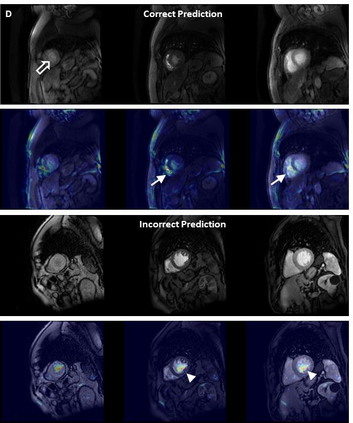

Objectives: To develop an image-based automatic deep learning method to classify cardiac MR images by sequence type and imaging plane for improved clinical post-processing efficiency. Methods: Multi-vendor cardiac MRI studies were retrospectively collected from 4 centres and 3 vendors. A two-head convolutional neural network ('CardiSort') was trained to classify 35 sequences by imaging sequence (n=17) and plane (n=10). Single vendor training (SVT) on single centre images (n=234 patients) and multi-vendor training (MVT) with multicentre images (n = 479 patients, 3 centres) was performed. Model accuracy was compared to manual ground truth labels by an expert radiologist on a hold-out test set for both SVT and MVT. External validation of MVT (MVTexternal) was performed on data from 3 previously unseen magnet systems from 2 vendors (n=80 patients). Results: High sequence and plane accuracies were observed for SVT (85.2% and 93.2% respectively), and MVT (96.5% and 98.1% respectively) on the hold-out test set. MVTexternal yielded sequence accuracy of 92.7% and plane accuracy of 93.0%. There was high accuracy for common sequences and conventional cardiac planes. Poor accuracy was observed for underrepresented classes and sequences where there was greater variability in acquisition parameters across centres, such as perfusion imaging. Conclusions: A deep learning network was developed on multivendor data to classify MRI studies into component sequences and planes, with external validation. With refinement, it has potential to improve workflow by enabling automated sequence selection, an important first step in completely automated post-processing pipelines.